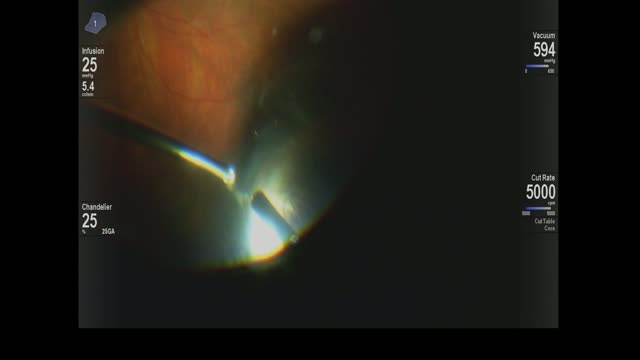

Scleral-Depressed Vitrectomy

Kourous A. Rezaei MD